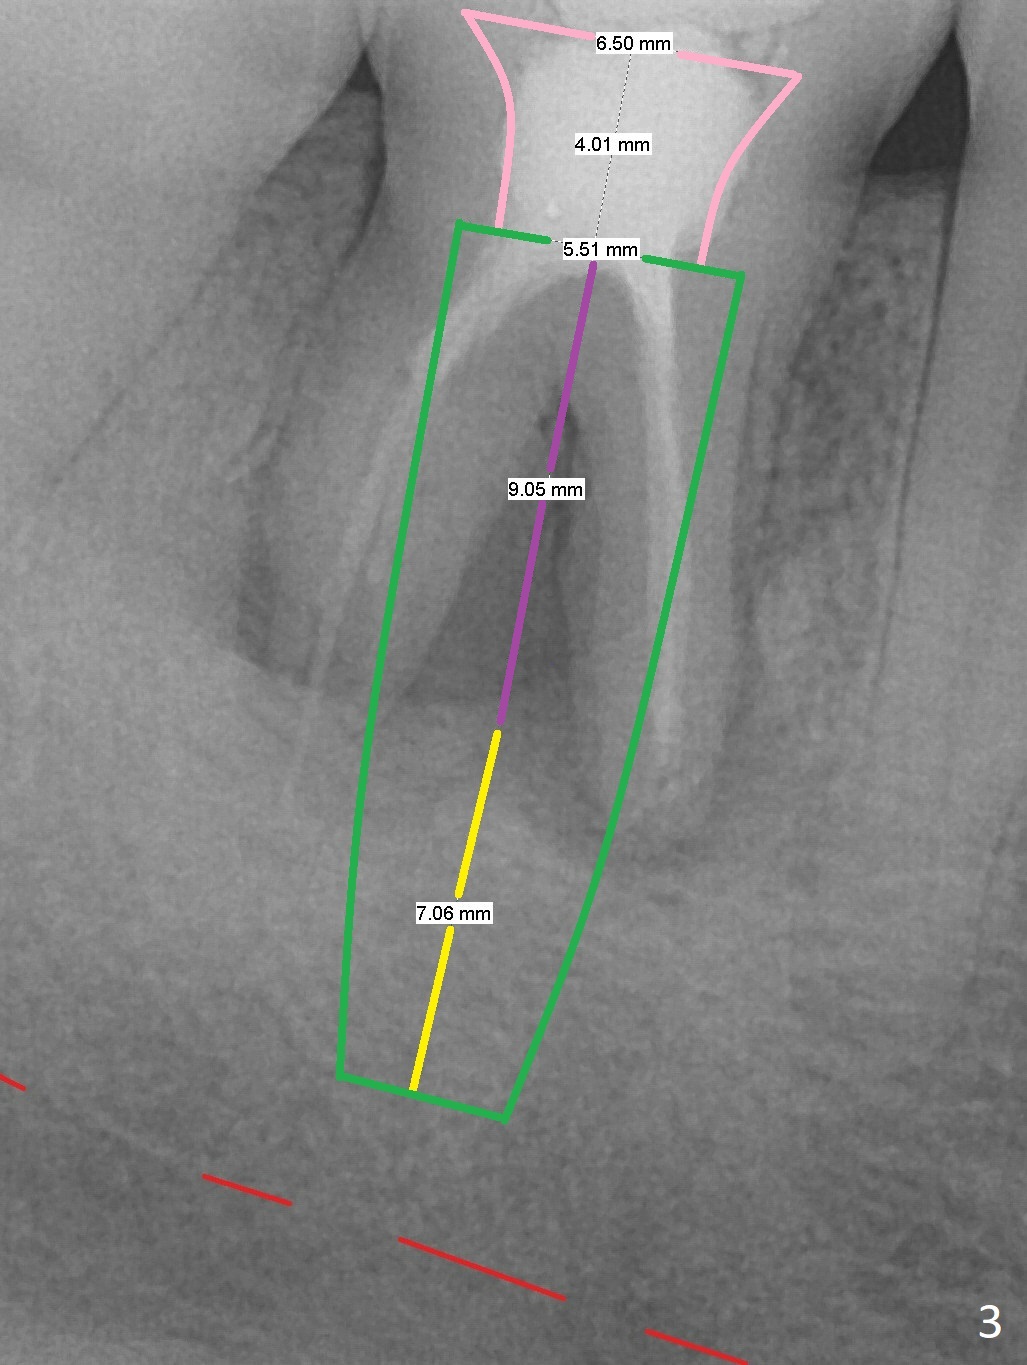

A 34-year-old man has a mobile molar post RCT (Fig.1,3) with lingual gingival recession (Fig.2). Possible bone defect is about 9 mm (Fig.3: purple line). There is approximately 7 mm native bone for primary stability (yellow line). Possible length of the implant to be placed will be 16 mm (9+7). Since the lingual gingiva is recessive (Fig.2), the osteotomy will be initiated more or less in the center of the socket bottom.